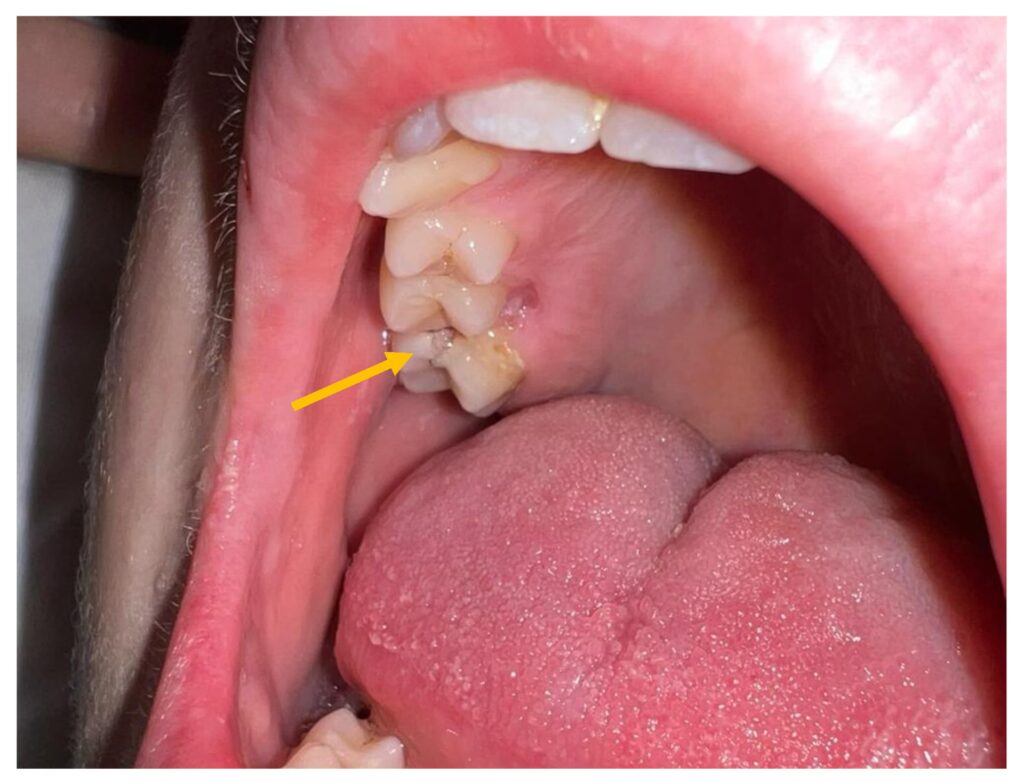

- Røde og hævede mandler, nogle gange med hvide pletter eller striber af pus

- Små røde pletter på den bløde eller hårde gane